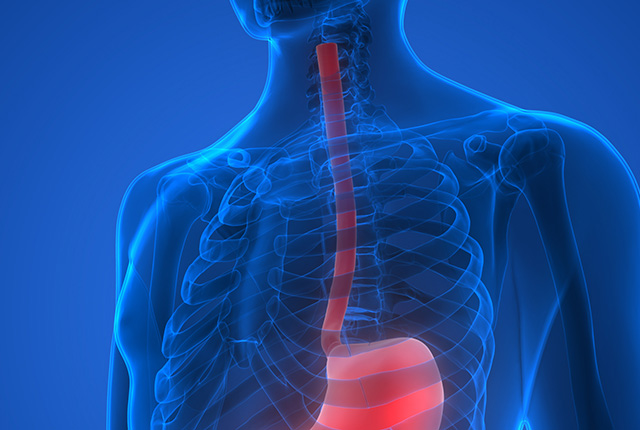

食道の疾患について

好酸球性食道炎(EoE)は、比較的最近になって定義付けされた新しい疾患で、好酸球性胃腸炎とともに好酸球性消化管疾患に分類されます。食道の粘膜に、アレルギー反応に関与する白血球の一種である好酸球が集簇することで生じ、特定の食物との関連も指摘されています。アレルギー性疾患である、気管支喘息・アレルギー性鼻炎・アトピー性皮膚炎との合併を認めることがあります。